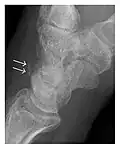

Triquetral fracture usually occurs on the dorsal aspect by impingement from the ulnar styloid or avulsion of strong ligamentous attachment. The dorsal avulsion fracture or "chip fracture" appears as a small bony fragment on the dorsal aspect of the triquetrum and is best detected on the lateral view(Figure 4). When radiography is negative in patients with high suspicion of a fracture, both MRI and MDCT will be of value. However, it has been shown that MRI is superior for detecting trabecular fractures in carpal bones.

-

a -

b

Figure 4: Dorsal triquetral fracture of the left wrist in a 30-year-old man after a trauma. (a) Anteroposterior radiograph shows a normal appearance. (b) Lateral radiograph of the same wrist demonstrates a chip fracture off the dorsal aspect of the triquetrum (arrow).[1]